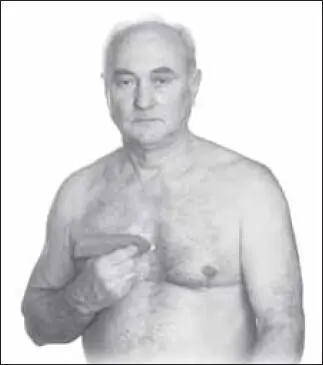

Воздействие седативное, расслабляющее, медленное, успокаивающее (1–2 минуты). Начинают с точки цзю-вэй (расположена на средней линии груди ниже конца мечевидного отростка грудины, на 7 цуней выше пупка вверх по средней линии) (рис. 129).